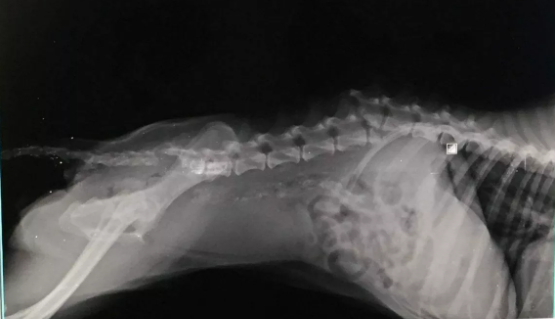

Faji i saj i vetëm? Të qenit endacake. Qenushja Mirushe është gjetur në kushte të mjerueshme në një lagje të Tiranës . Personat që e gjetën menduan se ishte përplasur nga ndonjë mjet dhe braktisur aty por jo, ajo ishte rrahur në mënyrë barbare, që “La Stampa” e cilëson si një dhunë të padëgjuar, pa arsye, që i shkaktoi një dëmtim të pakthyeshëm të shtyllës kurrizore.

Prej asaj dite, pesë vite më parë, Mirushja është gjysmë e paralizuar. Ajo u mbajt nga vullnetarë shqiptarë dhe falë Cinzias, një vullnetare toskane që kujdeset për një grup qensh me aftësi të kufizuara, mbërriti në Itali për të nisur një jetë të re, larg barbarisë që pësoi në vendin e saj. Por pavarësisht apeleve të shumta, askush nuk ka pasur kurrë guximin ti dalë zot, ndoshta i frikësuar nga gjendja e qenushes.

“Mirushja është një qenushe e lezetshme. Ajo erdhi nga Shqipëria në kushte të tmerrshme, me Ehrlichiosis të plotë (sëmundje e shkaktuar nga rriqrat) dhe Leishmaniozë (infeksion i rëndë) të padiagnostikuar.

Në Itali ajo filloi mjekimin dhe sot nuk i duhet më as të marrë ilaçe, thjesht duhet që gjendja e saj të mbahet nën kontroll”, thotë Cinzia.

Ajo ka edhe një karrocë me të cilën mund të lëvizë e pavarur për disa orë në ditë dhe ndonëse sigurisht që është traumatizuar nga eksperienca që ka pasur, nuk e tregon.